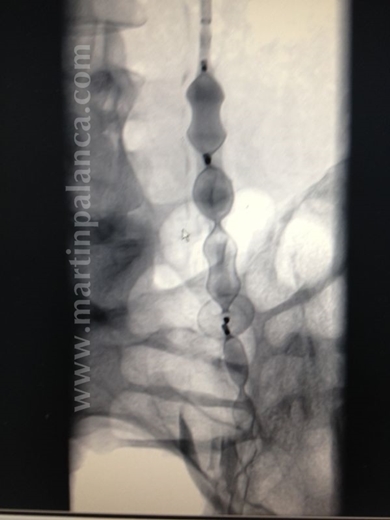

1ª)